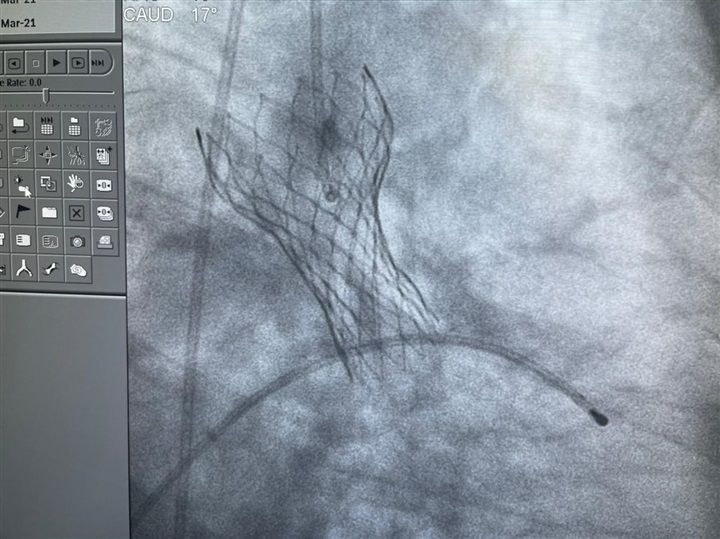

نجخ فريق طبي بمستشفى النصر التخصصي للأطفال، التابعة لهيئة الرعاية الصحية فى بورسعيد، في إجراء ثالث عملية استبدال صمام أورطي بالقلب باستخدام تقنية التافي (TAVI) لمُسِنة تبلغ من العمر 75 عامًا تحت مظلة التأمين الصحي الشامل.

واشارت الهيئة العامة للرعاية الصحية، إلى أن تقنية (التافي) هي أحدث التقنيات المستخدمة لعلاج أمراض القلب، ومن أحدث ما توصل إليه العلم في عمليات استبدال الصمام الأورطي، والتي تعني استبدال الصمام من دون شقّ منطقة الصدر، وذلك عن طريق القسطرة دون اللجوء إلى الجراحات التقليدية كالتدخل الجراحي في جراحات القلب المفتوح.

وأضافت أنه تم إجراء عملية استبدال الصمام الأورطي للمريضة عن طريق تقنية التافي؛ حيث كانت تعاني من ضيق شديد بالصمام، إضافة إلى إصابتها بمرض السكري والسمنة المفرطة وارتفاع ضغط الدم، والذي أدى إلى صعوبة التعامل مع الحالة المرضية جراحيًا وعدم اللجوء إلى الجراحات التقليدية واستبدالها بتقنية التافي؛ حفاظًا على حياة المريضة.

واستكملت الهيئة، أن مستشفى النصر التخصصي التابعة لها ببورسعيد أجرت عملية استبدال الصمام الأورطي للمريضة عن طريق تقنية التافي وهي من جراحات القلب المعقدة، بتكلفة مساهمة 300 جنيه فقط لا غير؛ حيث إنها من منتفعي التأمين الصحي الشامل بالمحافظة، وأنه تتجاوز تكلفة إجراء مثل هذه العمليات في مستشفيات القطاع الخاص سواء بمصر أو خارجها الـ500 ألف جنيه.

وأكد الدكتور أحمد السبكي، رئيس مجلس إدارة الهيئة العامة للرعاية الصحية، مساعد وزير الصحة والسكان، المشرف العام على مشروع التأمين الصحي الشامل، أن عملية استبدال الصمام الأورطي بالقلب عن طريق تقنية التافي (TAVI) تعد من العمليات فائقة الدقة التي يحتاج إجراؤها إلى خبراء في مجال القسطرة القلبية، مشيدًا بما تحتويه مستشفى النصر التخصصي التابعة للهيئة ببورسعيد من عناصر طبية متميزة وأطقم طبية ماهرة وتقنيات وتجهيزات طبية على أعلى مستوى بوحدة قسطرة القلب في المستشفى، والتي أصبحت تُحاكي أكبر وحدات القلب العالمية بشهادة الخبراء العالميين المتخصصين.